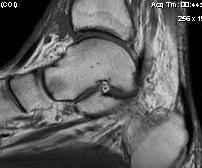

MRI

Edema / scarring / synovial thickening / fat alterations in sinus tarsi

Tears of interosseous / cervical ligament